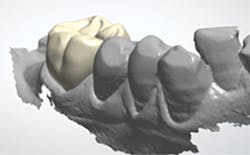

The next day, a good case opportunity presented itself. I had to prepare and scan No. 13 for a crown. I figured it was anteriorly positioned enough that I could test the esthetics, but it was posterior enough that the stakes weren’t too high. Nevertheless, you can see from Figures 1a–1c that we were thrilled with the results. Additional restoration examples can be seen in Figures 2 and 3.

Figures 1a–1c:

1a: Prepared No. 13, 1b: True Definition scan merged with clinical photo, 1c: No. 13 with Lava Esthetic full contour zirconia crown